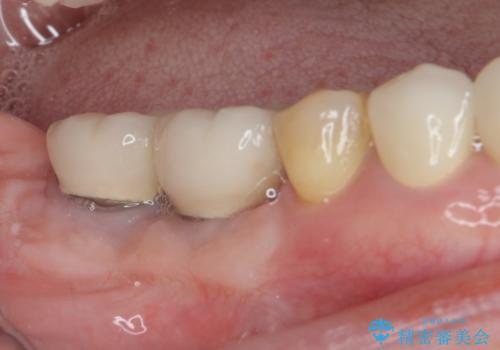

[歯周病治療] 歯周補綴 インプラント補綴

![[歯周病治療] 歯周補綴 インプラント補綴の症例 治療後](https://seimitsushinbi.jp/wp/wp-content/uploads/2020/03/93a1bf8bd8e0f11621dbb40f6f1d795c-500x350.jpg?v=1585494318)